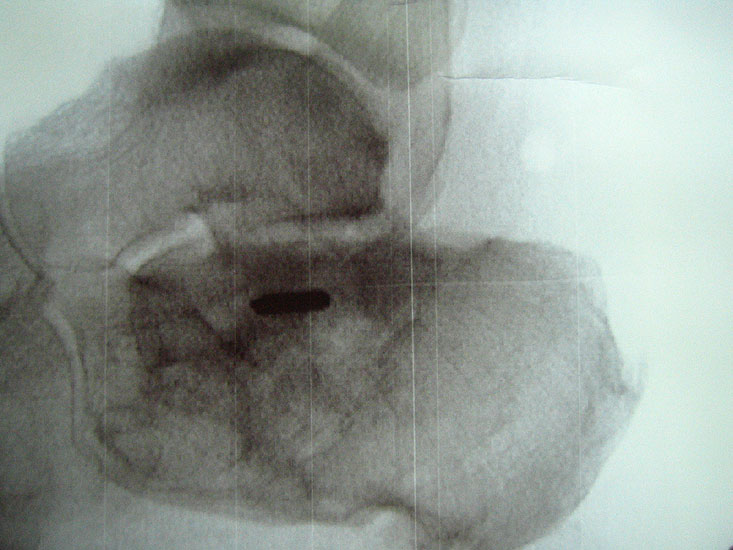

Abbildung Nr. 19-22

Knochenresektat sowie präoperatives CT (Sagittal- und Transversalebene) und intraoperative Bildwandlerkontrolle im seitlichen Strahlengang nach arthroskopischer Entfernung multipler Ossikel am dorsalen OSG/USG.

Abbildung Nr. 23 und 24, Video Nr. 4

Große osteophytäre Anbauten, welche die FHL-Sehne vollständig ummauern, sind ebenfalls sehr gut in der beschriebenen Technik adressierbar. Präoperatives CT und intraoperative Bildwandlerkontrolle im seitlichen Strahlengang (linke Seite).